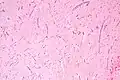

| Micrograph of an atrial myxoma. H&E stain. | |

Atrial myxoma and myocardium. H&E stain. -

Atrial myxoma. H&E stain. -

Atrial myxoma covered by endothelium. H&E stain.